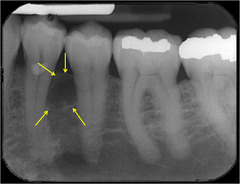

focal sclerosing osteomyelitis

-asymptomatic, bone adjacent to any tooth radiopaque area below roots -Mandibular 1st molar most common